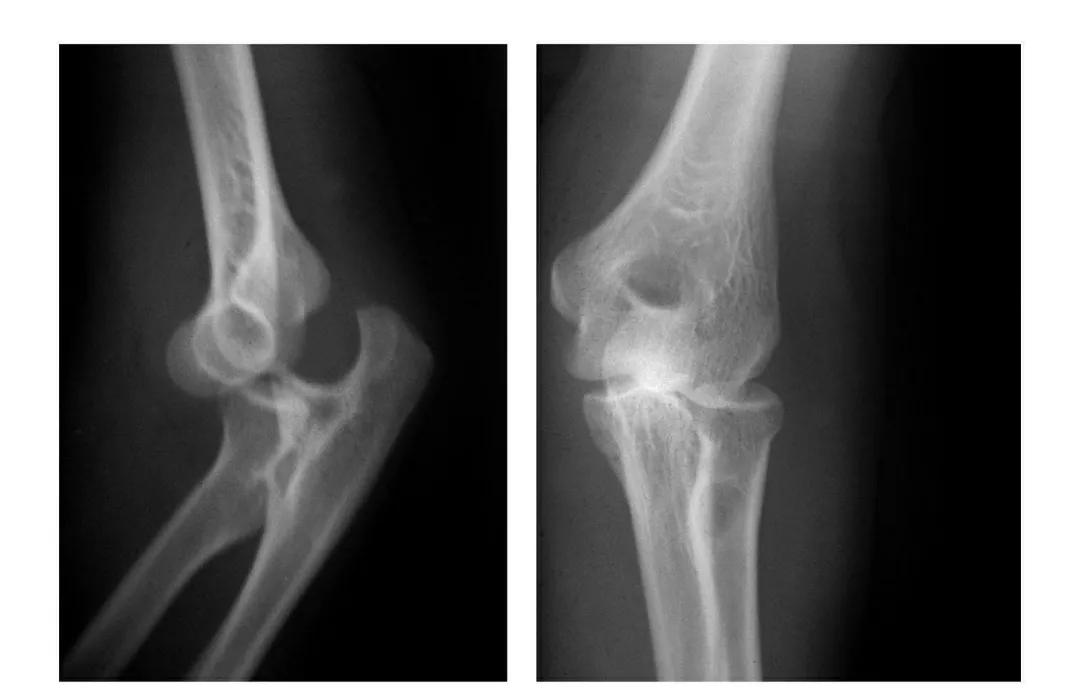

例3:肱骨小头及滑车桡侧壁前半部呈整体性冠状面骨折,骨折块向前上移位并外髁骨折。

(二)部分骨折

本病亦称科-洛(Kocher-Lorenz)型骨折

例1:肱骨小头软骨面及其下方少量骨质呈“新月样”被剥脱,且向肘前上方移位并桡骨头前半部骨折。

例2:肱骨小头软骨面剥脱性骨折,致该小头新月状骨片被向前脱位的桡骨头顶向肘关节前上方,并尺骨干中段骨折(孟氏伸展型骨折)。